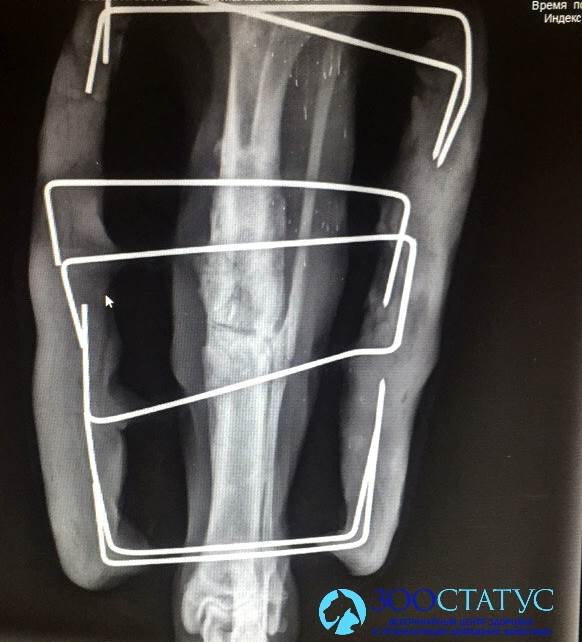

Во-первых, остеосинтез - процедура, направленная на стабилизацию перелома. При грамотном исполнении конструкция может выдерживать нагрузки, аналогичные нагрузкам на здоровую конечность. Поэтому нет необходимости переживать, что спицы или пластины сломаются.

Методы реабилитации могут помочь и при запущенных переломах, когда уже образовались контрактуры - улучшить эластичность связок, кровообращение в пораженной конечности, и, как следствие, сделать жизнь собаки более комфортной. При переломах, которые невозможно стабилизировать при помощи остеосинтеза (например, при переломах по типу зеленой ветки вследствие вторичного гиперпаратиреоза, когда кости низкой плотности просто не дадут возможности зафиксировать пластины или спицы) необходимо тщательное ограничение подвижности. Однако и в этом случае существует ряд методов реабилитации, которые позволят предотвратить вторичные дегенеративные изменения.